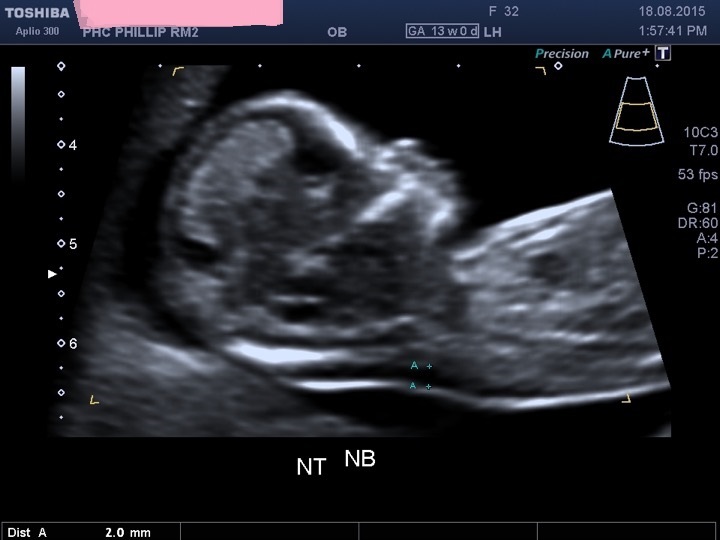

Nt エコー

先天異常部より Nt Nuchal Translucency について 医療者向け 日本産婦人科医会

Nt Nuchal Translucency ある産婦人科医のひとりごと

14 初期の超音波マーカー検査 日本産婦人科医会

先天異常部より Nt Nuchal Translucency について 医療者向け 日本産婦人科医会

02 妊娠初期 胎児の頸部浮腫 Nt 妊娠11 13週でcheck 深谷産婦人科 医学情報

胎児超音波ーマーカー検査とは ヒロクリニック

胎児の首の後ろのむくみ 浮腫 Nt とは 妊娠初期 All About

Nt Nuchal Translucency について 出生前検査 Nipt 遺伝カウンセリング 妊婦健診 エコー検査 産科 婦人科 産婦人科

胎児の首の後ろのむくみ 浮腫 Nt とは 妊娠初期 All About

胎児の首の後ろのむくみ 浮腫 Nt とは 妊娠初期 All About

胎児の首のむくみ Nt クリフム夫律子マタニティクリニック